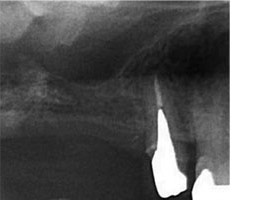

X光顯示垂直骨頭高度不足